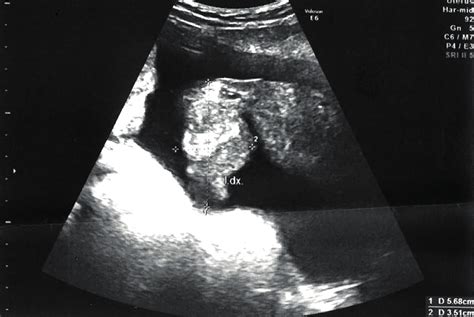

Na ultrazvuku je dobře vidět plod a slyšet jsou jeho srdeční ozvy. Těhotná žena na sobě pozoruje změny, především na prsou. Ta jsou citlivá, plnější, jsou viditelné žilky, tmavé prsní dvorce a bradavky. Je vhodné pořídit podprsenku pro těhotné a prsy ošetřovat. Mohou se vyskytovat změny nálad a přecitlivělost. Těhotenský hormon se v této době dostává na svůj vrchol.

Miminko roste do délky, dokončuje se vývoj části vnitřních orgánů. Hlava je v poměru ke zbytku těla stále velká, formuje se lebka, vyvíjejí se oči. Dále se vyvíjejí kosti. Některé orgány jsou již funkční. Výrazná je páteř a žebra. V tomto týdnu by budoucí maminka měla dostat těhotenskou průkazku. Je již možný první screening genetických poškození plodu. To se provádí ultrazvukem a rozborem krve. Výsledkem je stupeň rizika genetických vad a Downova syndromu. Provádí ho specializovaný lékař, který v případě nějakých zjištění navrhne další postup. U větších rizik se provádí i odběr plodové vody.

Miminku rychle rostou ruce, končetiny jsou obecně hubené. Pohlaví se vyvíjí, ještě ho však nelze spolehlivě určit. Na povrchu těla miminka se tvoří jemné ochlupení. Děťátko se lehce hýbe, ale maminka tyto pohyby ještě necítí. Pohyby jsou vidět na ultrazvuku. Plod polyká plodovou vodu a ledvinami ji zase vylučuje.

Miminko má tělo kompletně porostlé kůží. Lze již stanovit pohlaví plodu. Miminko se již zřetelně pohybuje. Maminka je cítí slabě, ale na ultrazvuku jsou zřetelné. S druhým trimestrem přicházejí obtíže s trávením, zácpa, na kůži se objevuje zřetelná pigmentace a skvrny. Ty většinou po porodu mizí. Důležitý je pravidelný pohyb, dostatek vlákniny ve stravě a patřičná dávka tekutin.

Miminko stále vyrovnává proporce těla, má založené mléčné zuby a začínají se vyvíjet základy trvalých zubů. Ovládá již obličejové svaly, pohybuje rty. Kůže má všechny základní vrstvy a pigment. V tomto období by měl proběhnout druhý screening ultrazvukem. Zjišťují se vývojové vady, růst miminka, množství plodové vody a poloha placenty. Pokud je to potřeba, proběhne i vyšetření srdce. Maminka může po ultrazvuku dostat obrázek miminka.